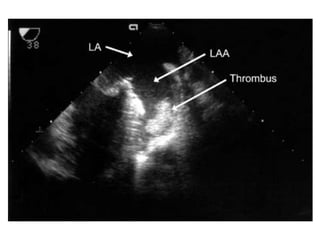

Identification of concomitant lesions.

• The quantitation of left atrial enlargement

favours 2D echocardiography enabling left atrial

area or volume to be evaluated.

• Left atrial spontaneous contrast as assessed by

TEE is a better predictor of the thromboembolic

risk than left atrial size.

Transoesophageal echocardiography

Recommended only when the transthoracic

approach is of poor quality, or to detect left

atrial thrombosis before balloon mitral

commissurotomy or following a

thromboembolic event.

Identification of concomitantlesions. • The quantitation of left atrial enlargement favours 2D echocardiography enabling left atrial area or volume to be evaluated. • Left atrial spontaneous contrast as assessed by TEE is a better predictor of the thromboembolic risk than left atrial size. • Associated MR has important implications for the choice of intervention • mediate severity since more than mild regurgitation is a relative contraindication for balloon mitral commissurotomy

Transoesophageal echocardiography Recommended onlywhen the transthoracic approach is of poor quality, or to detect left atrial thrombosis before balloon mitral commissurotomy or following a thromboembolic event.